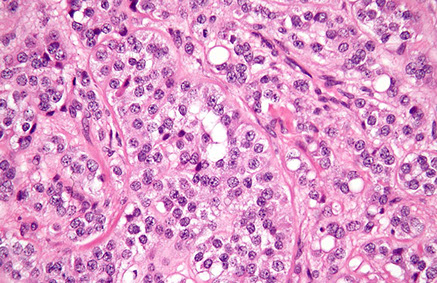

Use of immunohistochemistry in diagnosis of germ cell tumor (GCT). A, A mixed GCT with embryonal carcinoma and yolk sac tumor (YST) components. B, Immunostain of OCT4 is positive in the embryonal carcinoma, negative in the YST. C, Immunostain of GPC3 is positive in the YST and negative in the embryonal carcinoma [2]

[2]